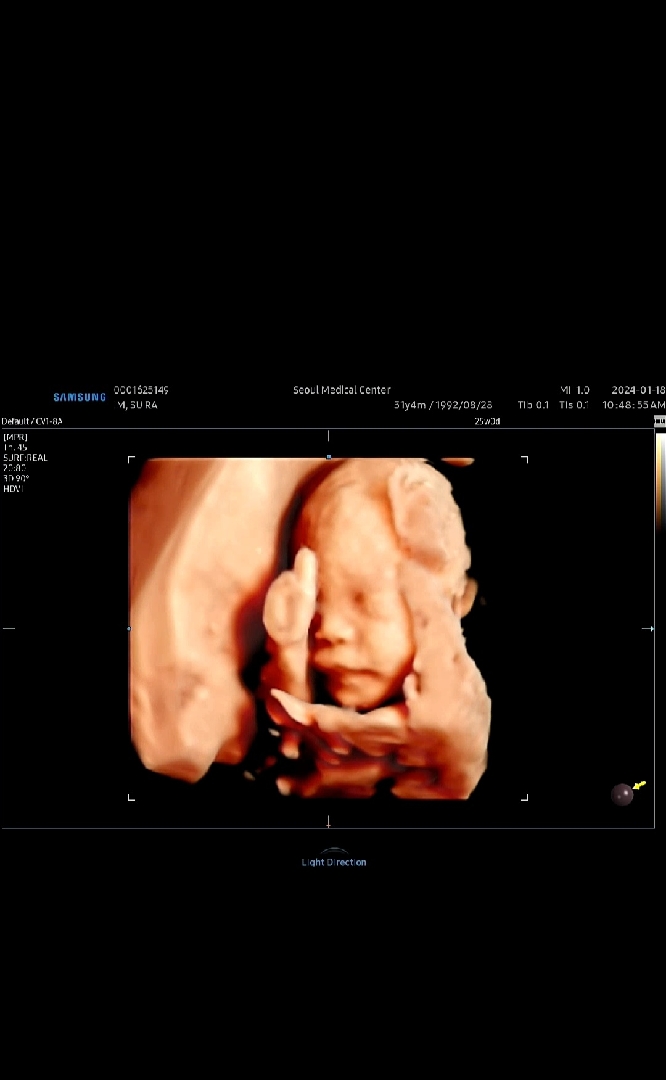

입체초음파 찍었어요😖

찍은지 몇일지났는디 자랑하구싶어서 올려봐용ㅎㅎ 열무가 따봉해줬어요(งᐛ)ว (งᐖ )ว ㅋㅋㅋㅋㅋㅋㅋㅋㅋㅋㅋㅋ 얼굴 안보여줄까봐 걱정했는데 너무 신기해요ㅋㅋㅋㅋㅋ 남편이 사진찍을때 항상 따봉하는데 그아빠에 그아들이라 그런가 하고 한참웃었어욬ㅋㅋㅋㅋㅋㅋㅋㅋㅋ😆😆